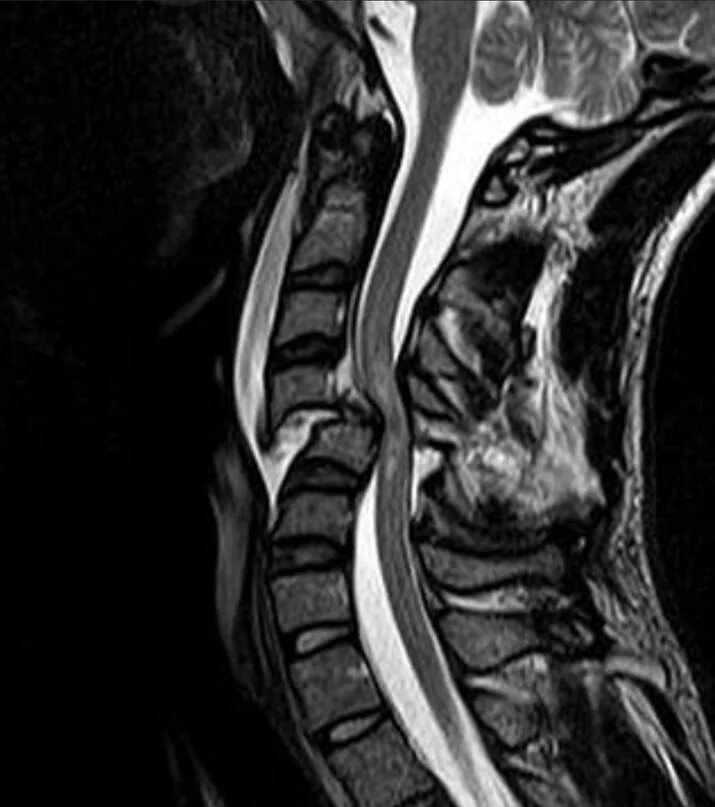

В шейном отделе мрт